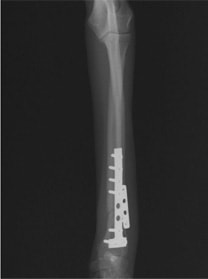

Advanced Locking plate system と Locking compression plate system

当院ではAdvanced Locking plate system(ALPS)と、Locking compression plate system(LCPS)という骨接合法で骨折症例の治療を行っています。

Advanced Locking Plate System

従来型のプレートのように広い面積で骨と接するプレートを用いて固定を行った場合、プレート下の骨はプレートとの接触面において血行が絶たれ壊死し、それがリモデリングされると骨密度が低下する。この骨密度の低下防ぐために、骨折部局所への血行を温存することの重要性が近年改めて認識されるようになってきている。Advaed Locking Plate System (ALPS)は従来型のプレートシステムの欠点を改良し、より使いやすく、より骨への血行を阻害しないようにというコンセプトで作られた。

Advanced Locking Plate System の特徴

- 骨への血行障害は最小限である

- 上下左右にベンディング可能でより3次元的な成形が可能

- すべての部位においてプレート強度は均一である

- ロッキングスクリューと圧着型スクリュー(皮質骨スクリュー)の双方が使用できる

- ダイナミックコンプレッション機能

- 生体親和性の高いチタン製

- トイ犬種から馬まで応用できるサイズ展開がある

トイプードル 右遠位橈尺骨短斜骨折のALPSによる内固定

Locking Compression Plate

LCPは、スクリュー(ネジ)とプレート(金属の板)をロックする特殊な構造により骨折部位を固定する新しい世代のプレートシステムです。ひとつのホールでロッキングスクリューとスタンダードスクリューの使用を選択できるユニークな構造をしているため、骨折断端間の圧迫を目的とした従来型プレート固定法に加え、高い角度安定性を有するロッキングスクリューを用いた固定法の選択が可能です。従来のプレートシステムでは困難だった部分の骨折や癒合不全の症例に高い治療効果をもたらします。